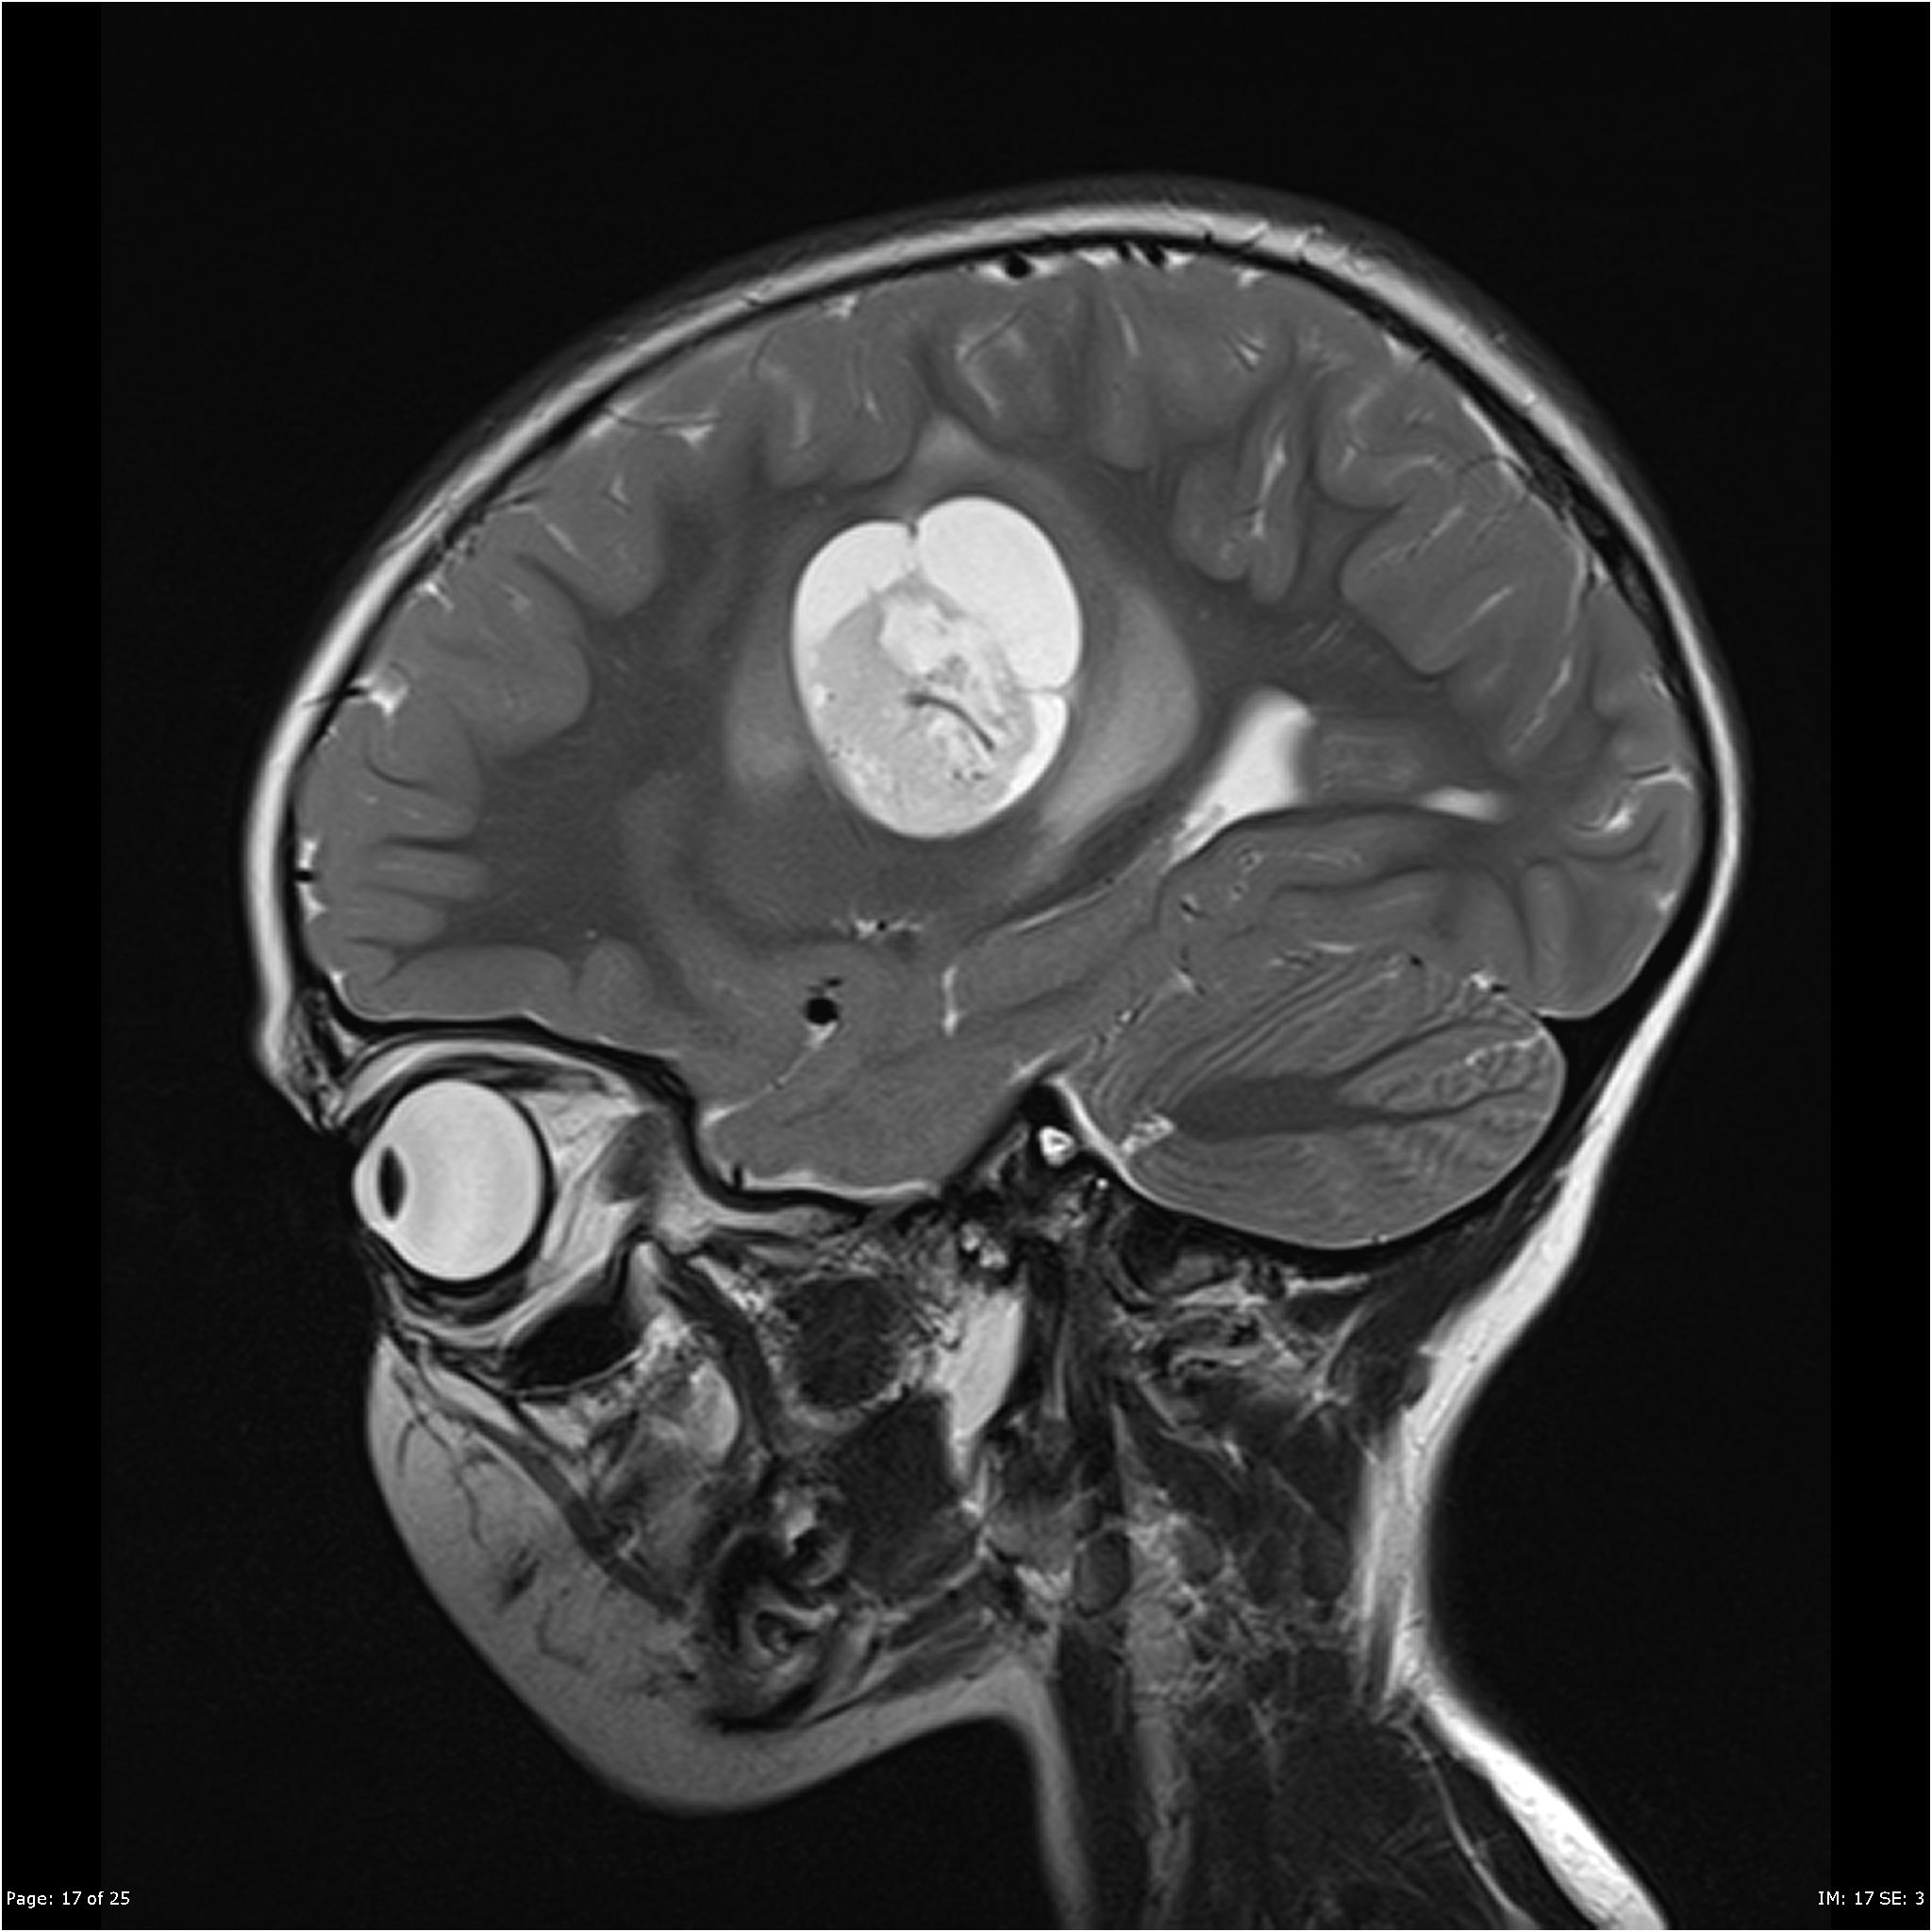

Микрофотографии гистологии глиобластомы головного мозга